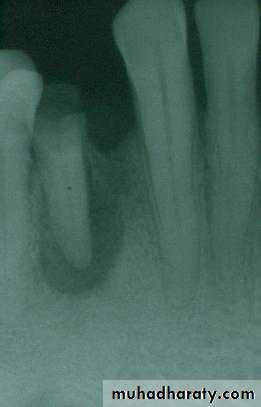

b. Removal of pathoses…cystic, traumatic, hyper-plastic, dysplastic, etc.